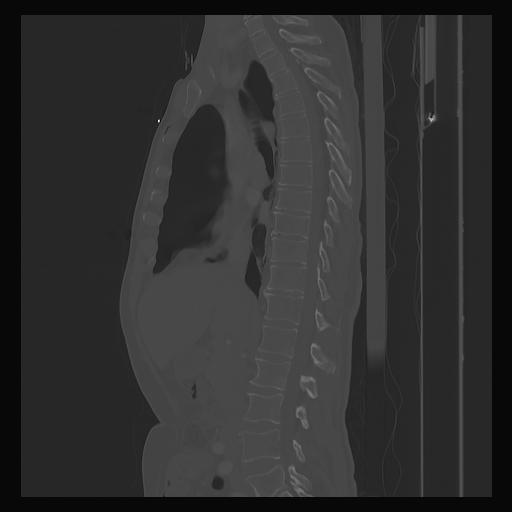

33 PULMON,CE,Sagittal,3.000,PULMON,Sagittal,